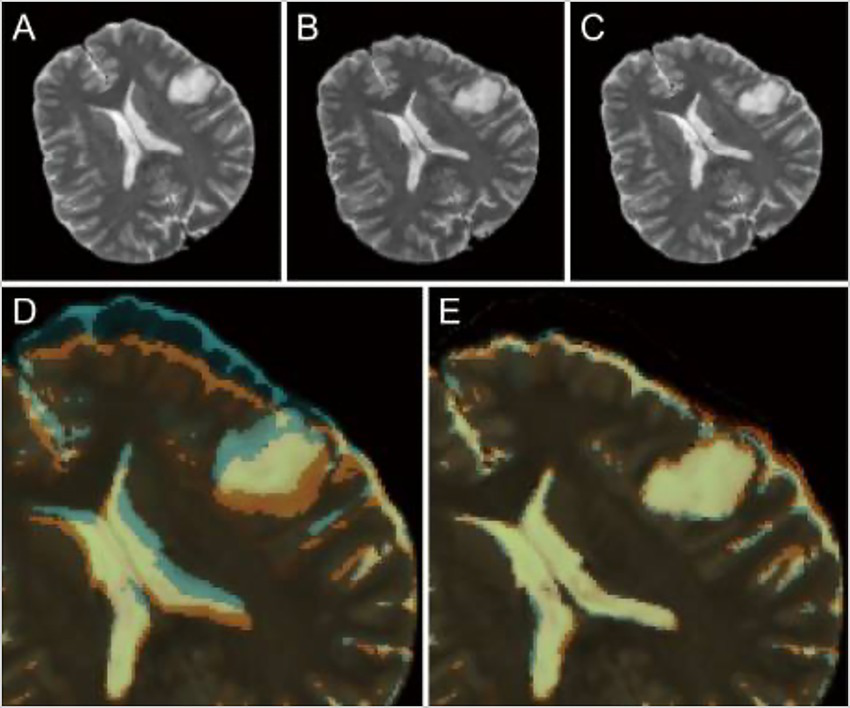

Neuronavigation during surgery is typically limited by brain shift following the incision and opening of the dura, which reduces the ability of neurosurgeons to identify their location intracranially during procedures. Shimamoto et al. used a CNN to design updated MRI to help remediate this issue (123). Preoperative and intraoperative MRI data from 248 patients was used, with the preoperative images serving as the training data for the CNN and the intraoperative images serving as the ground truth. This method allowed the model to learn how the brain shifted after the dural opening and adjust accordingly based only on preoperative images (Figure 7) (123).

Figure 7

Role of deep learning (DL) in enhancing neuronavigation systems. A study by Shimamoto et al. (123) focused on the ability of a convolutional neural network (CNN) to adjust for and predict brain shifts based on preoperative and intraoperative magnetic resonance imaging (MRI). This figure illustrates the process of predicting brain shift intraoperatively compared to preoperatively in a selected case from the study (case 47). (A) Preoperative T2-weighted MRI. (B) Intraoperative image of the corresponding T2-weighted MRI. (C) The corresponding updated MRI. (D) The overlay of both the preoperative and intraoperative MRIs. (E) The updated MRI and the intraoperative MRI. The purpose of this image is to show the ability of the W-Net DL system to compensate for the brain shift. Reproduced from Shimamoto et al., Neurol Med Chir (Tokyo), 2023. Licensed under CC BY-NC-ND 4.0.